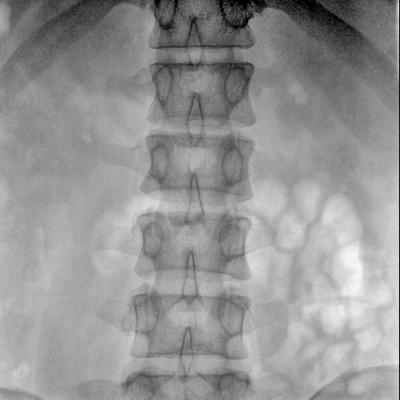

可用于常規(guī)的外周血管介入手術,設備的移動性好,對手術室空間要求低,可滿足長時間X光透視的需求,且增加了獨特的血管影像處理功能,是開展介入手術的理想設備。

優(yōu)質平板探測器、可靈活升降調節(jié)SID、獨特圖像處理系統(tǒng)、高品質濾線柵,大視野成像清晰不失真。

采用智能劑量控制技術,可根據(jù)不同體型和不同部位,準確調節(jié)投照劑量。使操作者在任何使用環(huán)境下,都能實現(xiàn)低劑量、診視圖像清晰的效果。